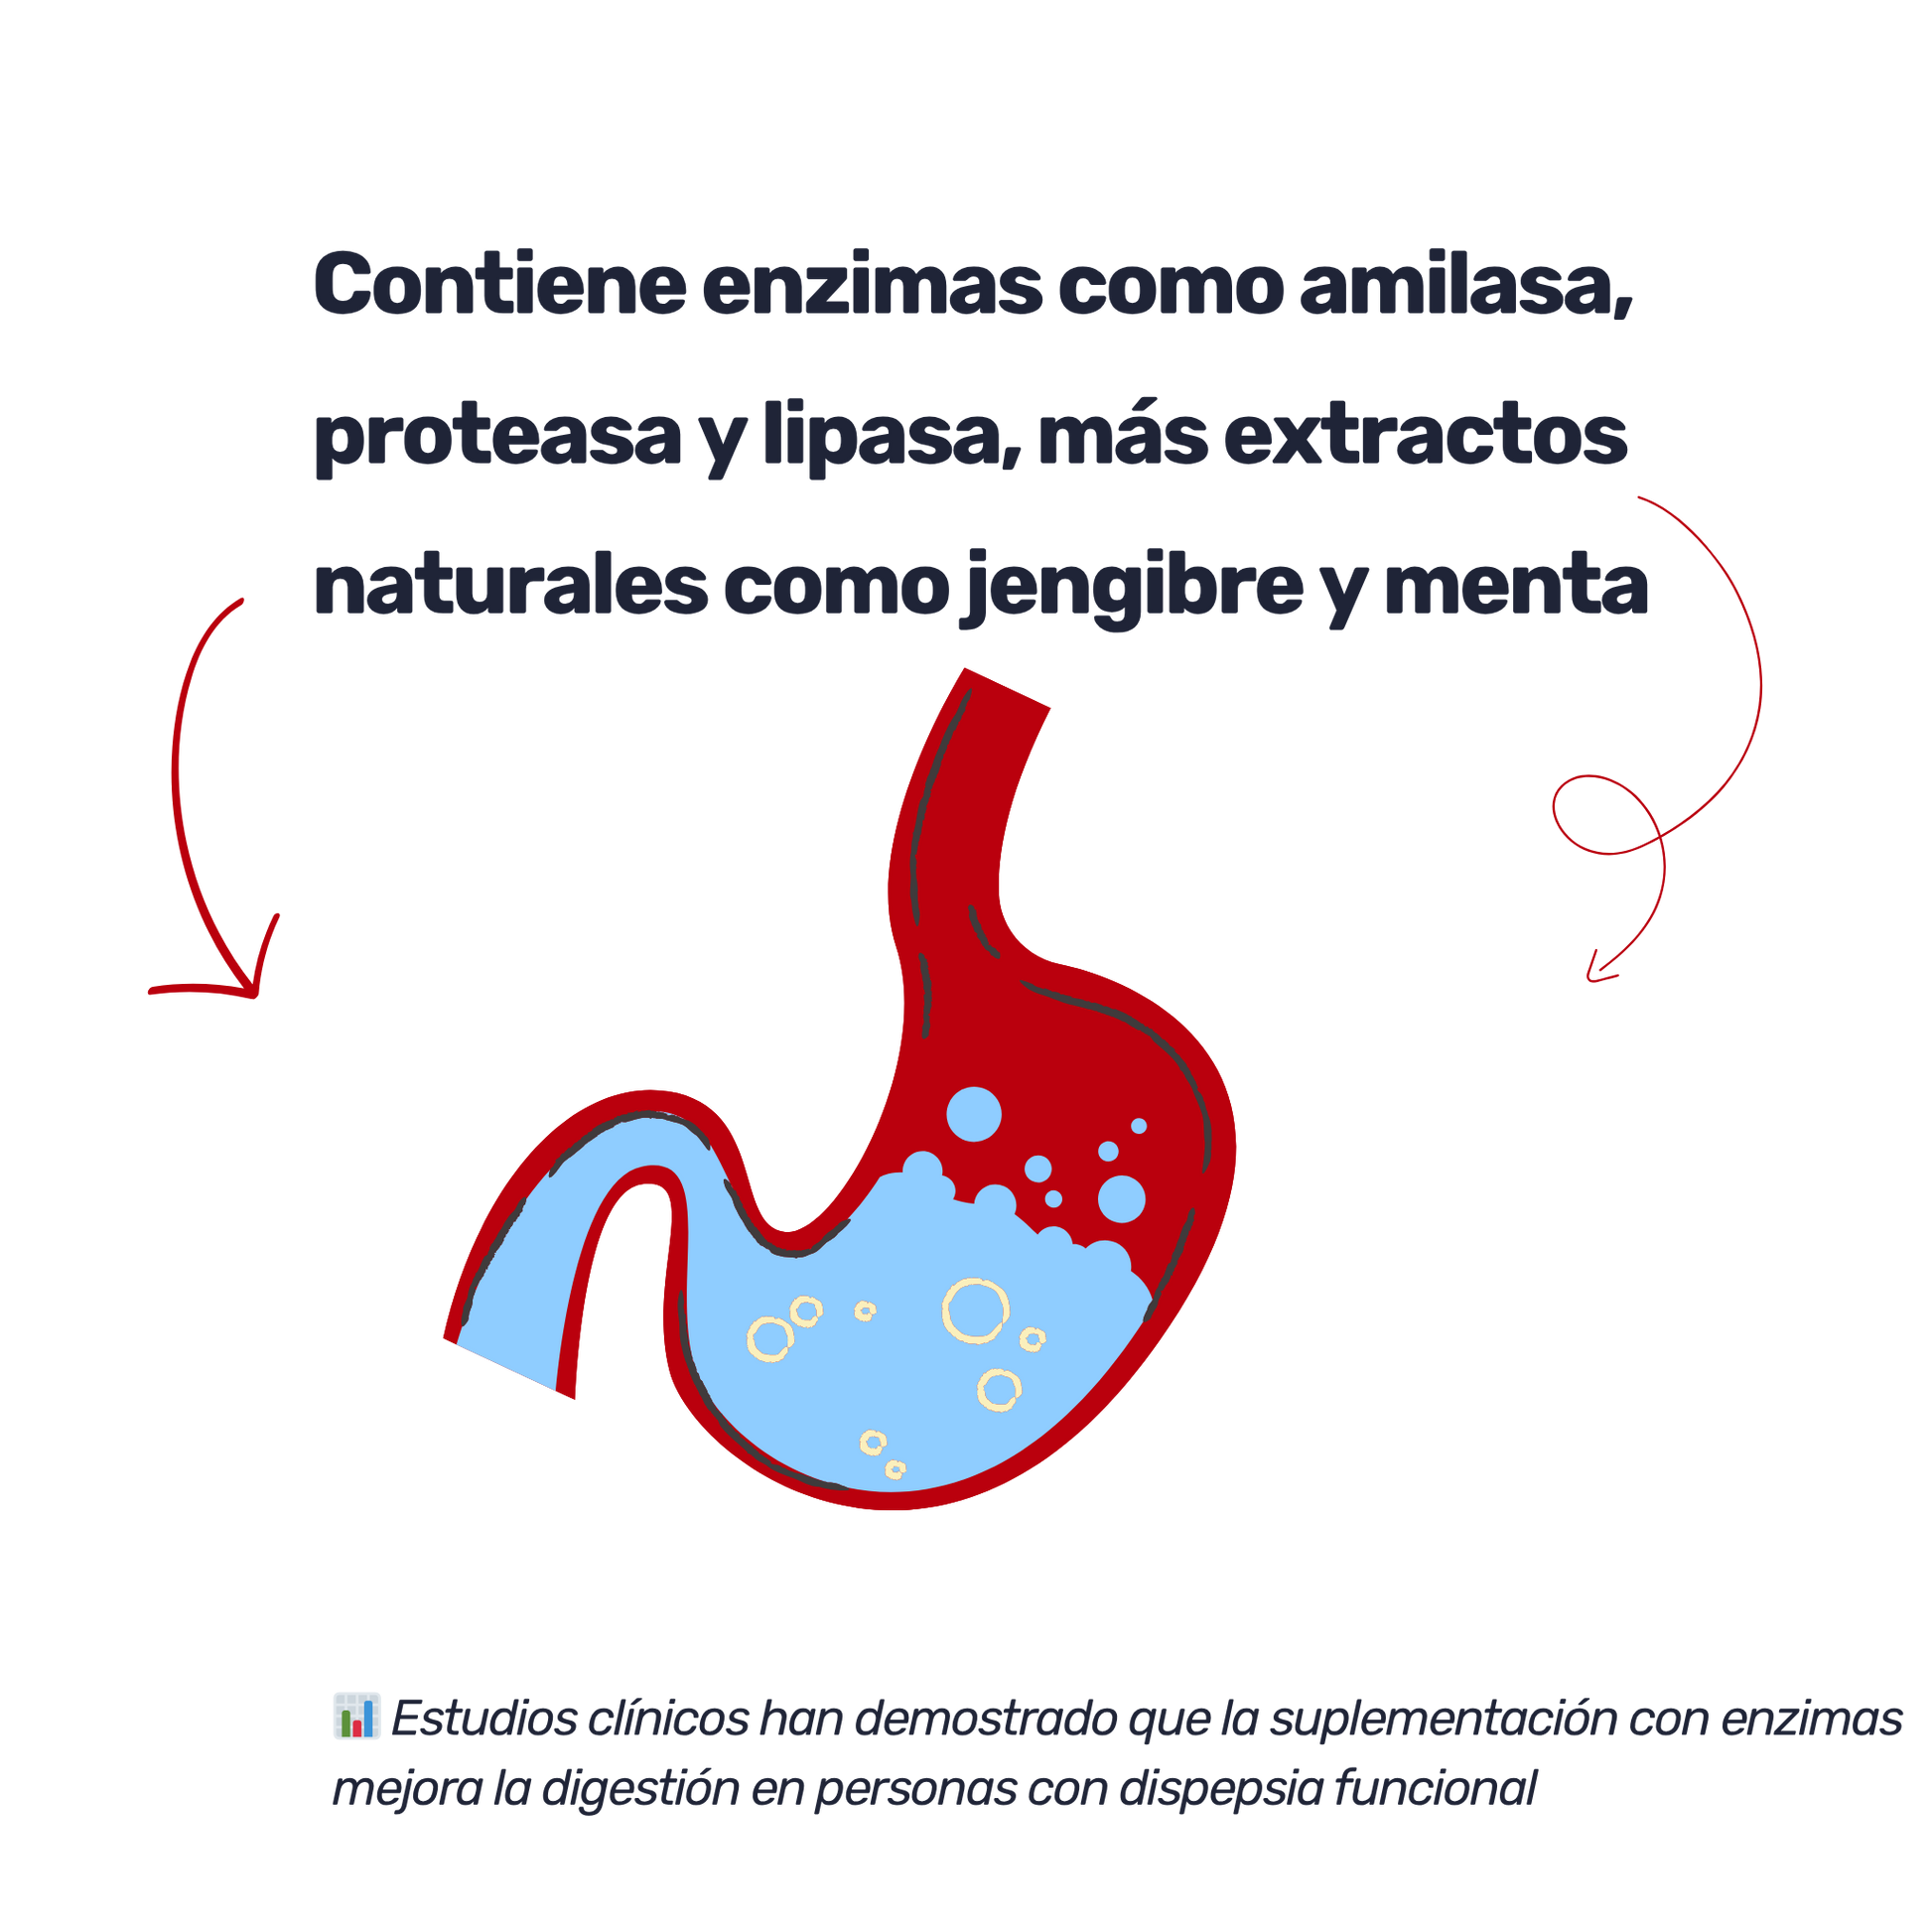

Un suplemento diseñado para apoyar el sistema digestivo cuando más lo necesitas. Las enzimas digestivas ayudan a descomponer proteínas, grasas y carbohidratos, facilitando la digestión y disminuyendo malestares como hinchazón, gases y reflujo. Especialmente útil en personas con digestión lenta, adultos mayores o quienes siguen dietas altas en proteínas. Esta fórmula combina enzimas esenciales con extractos de plantas digestivas para mejorar la absorción de nutrientes y promover una digestión más ligera y eficiente.

¿Que respaldo hay para su consumo? 🔬